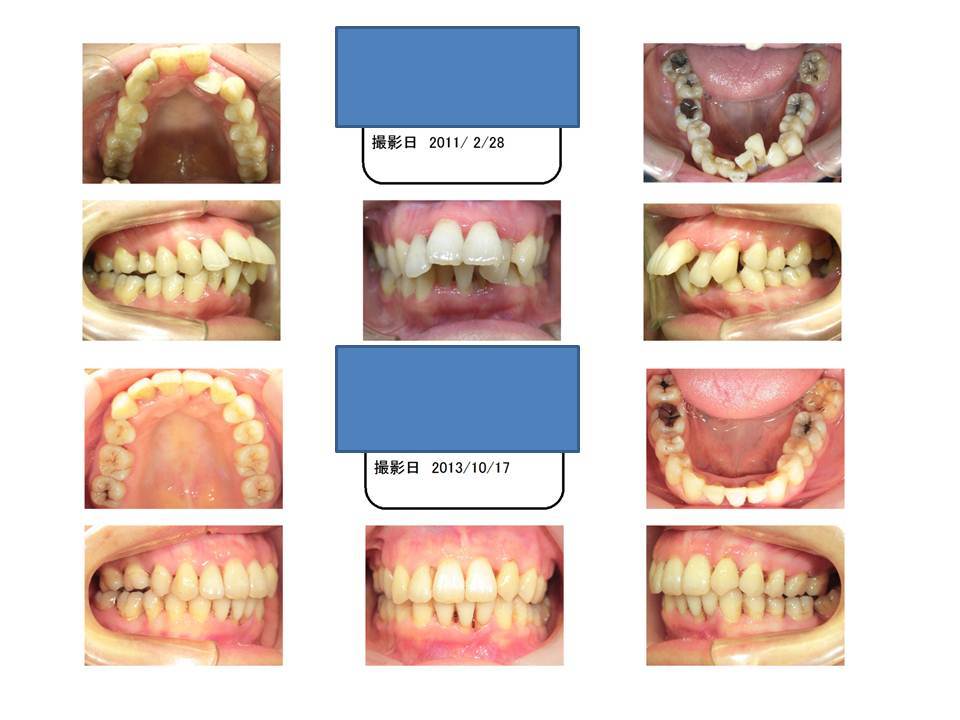

この症例の患者さんは、歯並びについて非常に悩まれていました。

他院では、治療の施しようがないよううな心に引っかかるような事を言われたようで、歯並びについては最初諦めていたようです。

当院に矯正の相談にお越し頂き、歯を抜く必要はありますが、歯並びの治療は可能だということをお伝えしました。

実際とても勇気を振り絞って矯正治療に臨まれたと思いますが、この変化を見てもらうと本人だけでなく、誰もが歯並びを治療して良かったと思うのではないでしょうか?

上下左右一本ずつ歯を抜いて隙間を作り、上下の前歯を後ろに下げ、口元を下げます。ブラケット装置にて治療。

最初の状態より上の口元は下がりますが、患者様が想像されているところまで必ずいくとは断言できません。